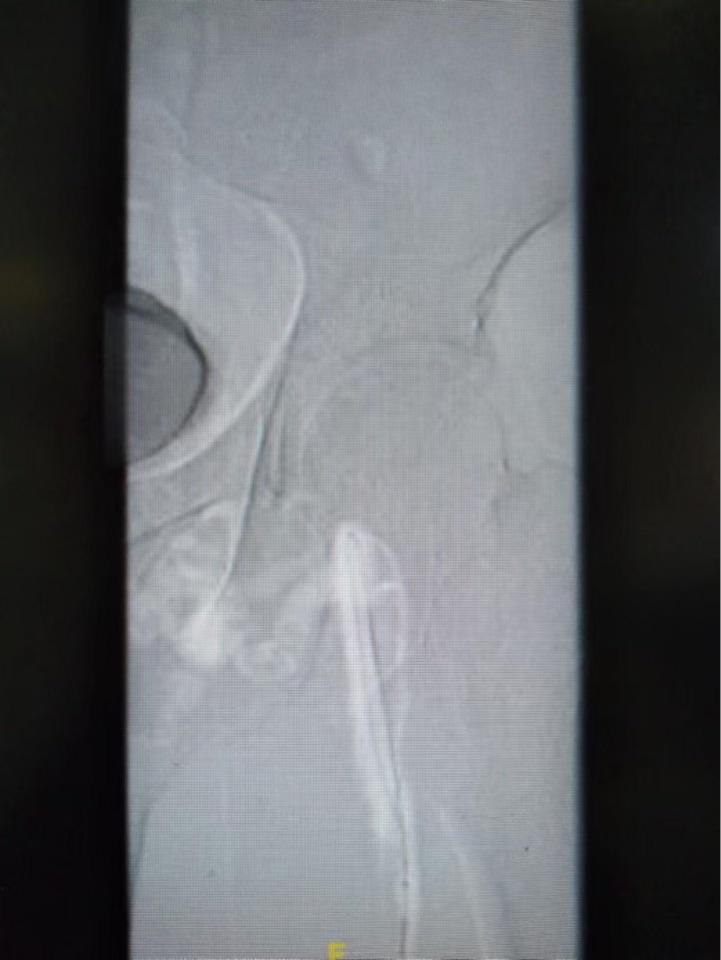

术中造影可见髂股静脉完全堵塞